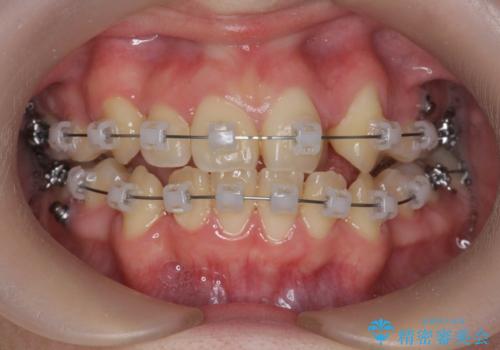

歯並びのせいで歯ブラシがしづらい マルチブラケットを用いた抜歯矯正

- 歯並びのがたつきにより歯ブラシがしづらく、今後虫歯になってしまう不安から、矯正治療を希望されて来院されました。

歯を並べるにはスペースが不足しているため、小臼歯の抜歯を4本行うマルチブラケット矯正による治療を計画します。

治療後は非常に歯ブラシがしやすくなったと、治療結果に満足いただくことができました。